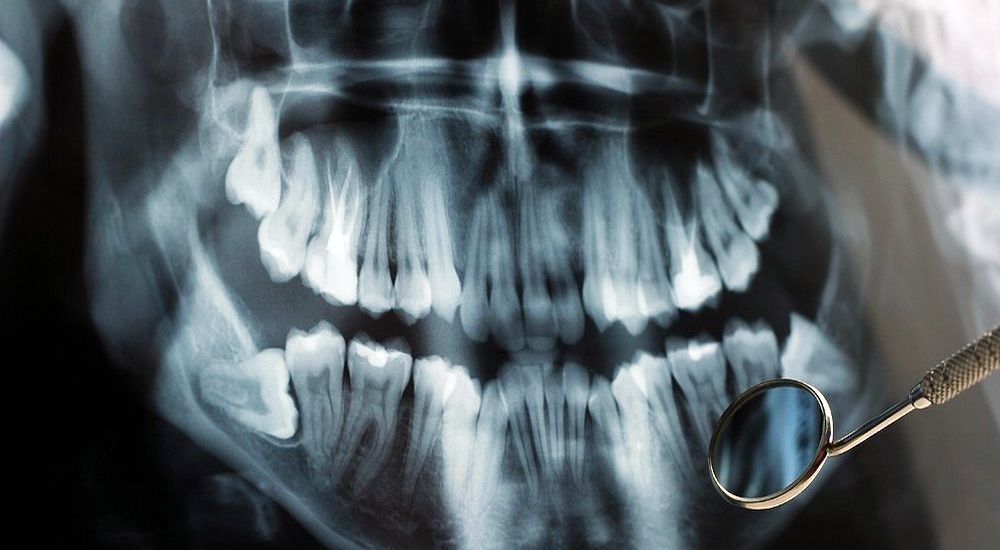

How Safe Are Dental X-Rays?

We have heard a lot of concern from people about radiation exposure from dental x-rays.

So how safe are dental x-rays? In the 70's & 80's x-rays were taken with small films.

With today's digital technology, exposure to radiation is more than 80% less.

It's like being out in the sun for a couple hours for a day. On top of that, with improved quality we can diagnose problems much sooner without invasive procedures to find problems beneath the surface.

It's a proven fact that our patients who have routine dental x-rays have fewer surprises when it comes to their dental care.